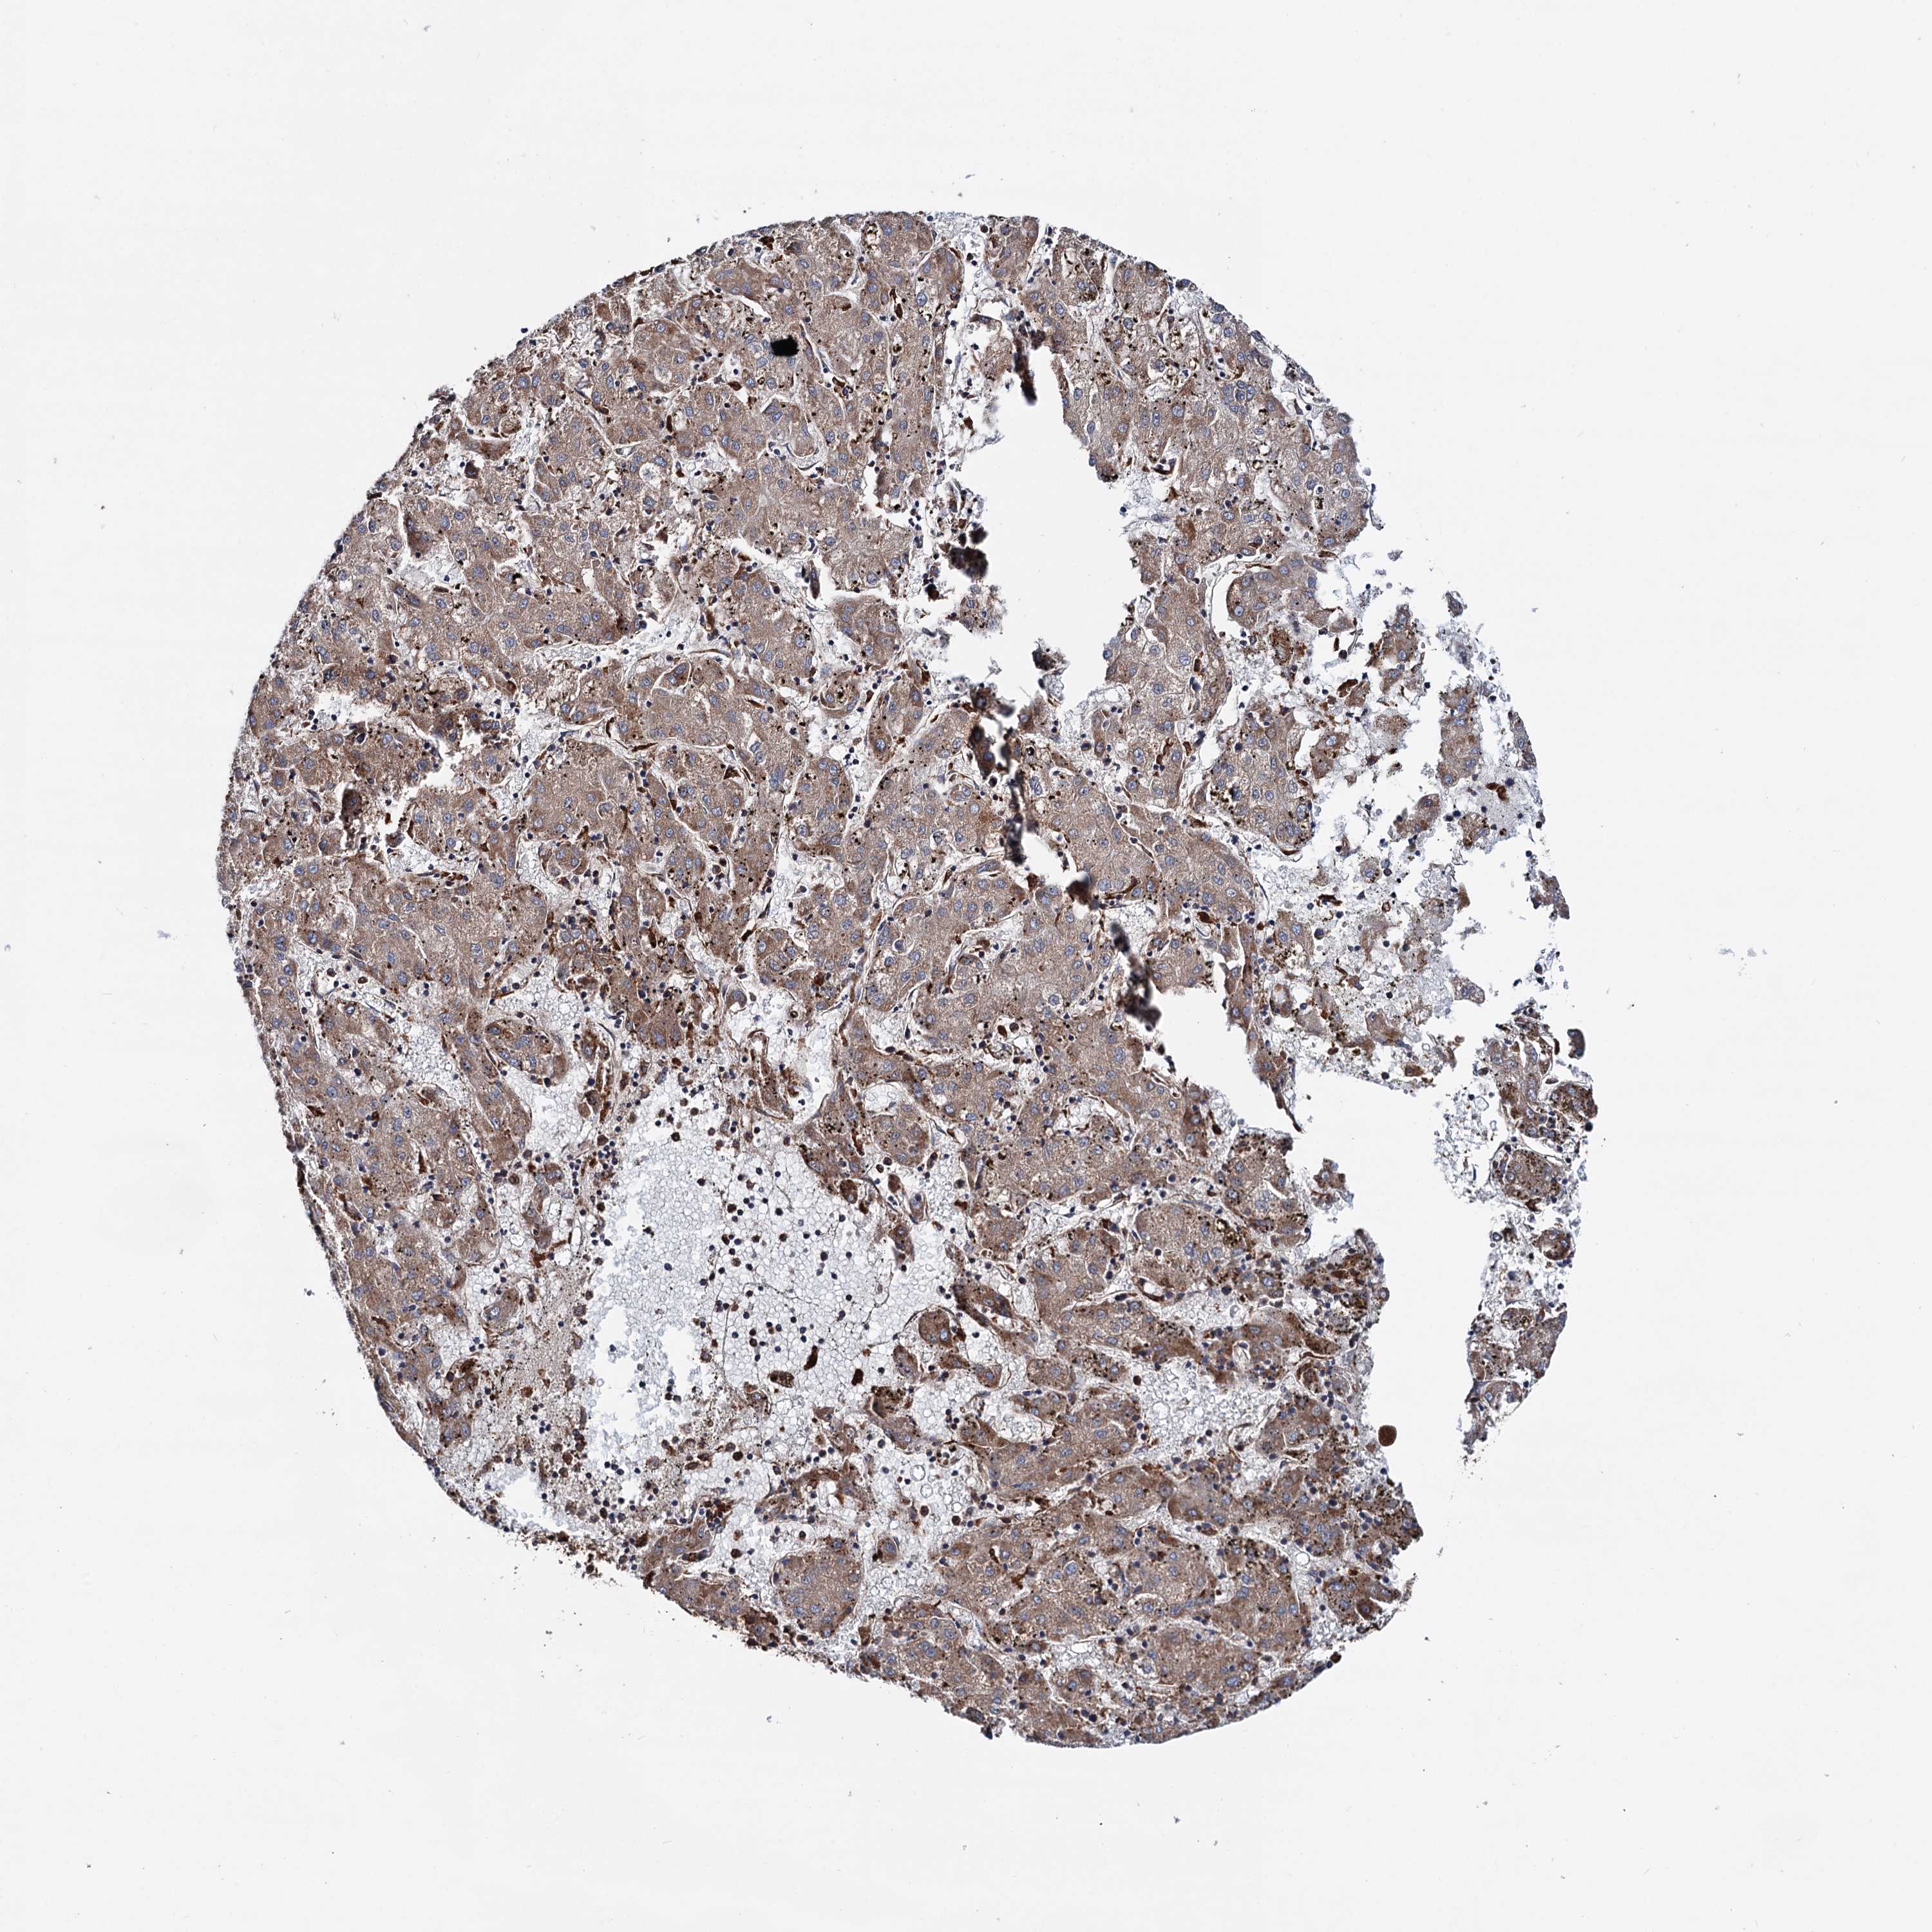

LIVER CANCER - Protein expressioni

A mouse-over function shows sample information and annotation data. Click on an image to view it in a full screen mode. Samples can be filtered based on level of antibody staining by selecting one or several of the following categories: high, medium, low and not detected. The assay and annotation is described here.

Note that samples used for immunohistochemistry by the Human Protein Atlas do not correspond to samples in the TCGA dataset.

Antibody stainingi

Antibody staining in the annotated cell types in the current human tissue is reported as not detected, low, medium, or high, based on conventional immunohistochemistry profiling in selected tissues. This score is based on the combination of the staining intensity and fraction of stained cells.

Each image is clickable and will lead to virtual microscopy that enables deeper exploration of all samples and also displays staining intensity scores, fraction scores and subcellular localization as well as patient and tissue information for each sample.

Antibody HPA039363

Antibody HPA039456

Staining

High

Medium

Low

Not detected

Intensity

Strong

Moderate

Weak

Negative

Quantity

>75%

75%-25%

<25%

None

Location

Nuclear

Cytoplasmic/membranous

Cytoplasmic/membranous,nuclear

Cholangiocarcinoma

Carcinoma, Hepatocellular, NOS